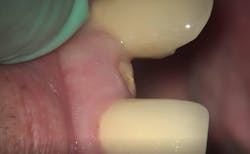

- Treatment plan: Extraction/immediate implant placement with nonfunctional provisional

- Implant: Ditron Ultimate 3.75 x 16 mm

- Abutment: Final straight 11.5 mm titanium abutment delivered at time of implant placement